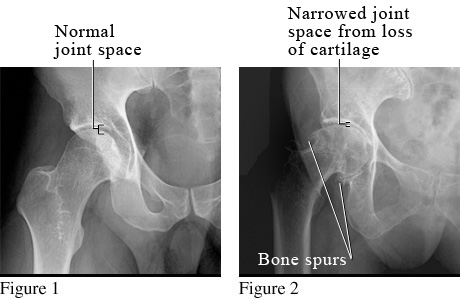

X-Ray of Osteoarthritis of the Hip

Figure 1 shows a normal hip.

Figure 2 shows osteoarthritis of the hip with loss of cartilage, narrowing of the joint space (the space between the bones), and bone spurs.